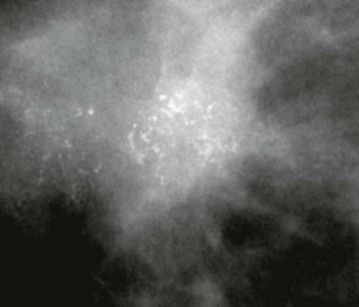

Benign-type microcalcification is coarse and ‘chunky’ (Fig. 45.6). Fine branching microcalcification is characteristic of ductal carcinoma-in-situ (DCIS). Architectural distortion and asymmetry are subtle radiological signs but should be viewed with suspicion.